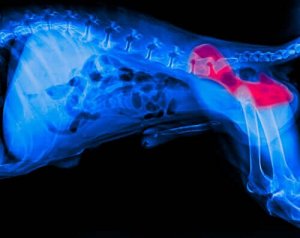

Dysplasi är i det här fallet ett tillstånd som drabbar höftlederna och det omkringliggande området. Det orsakas av en missbildning av lårbenshuvudet och den motsvarande höftleden.

När detta sker börjar leden försämras, vilket orsakar obehag och lamhet.

Tillståndet har en rad olika symptom. De vanligaste inkluderar lamhet, svårigheter att resa sig upp eller att hunden kontinuerligt står upp. Om du märker av dem måste du tala med en veterinär så att djuret kan röntgas.